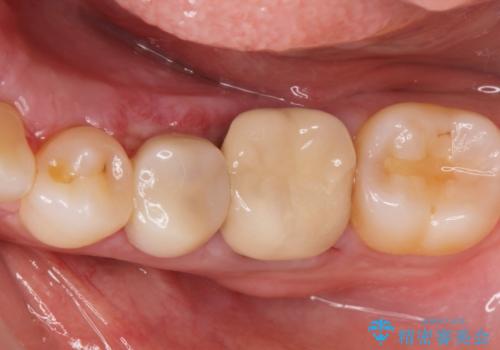

インレー下に再発した虫歯 セラミッククラウンによるやり替え